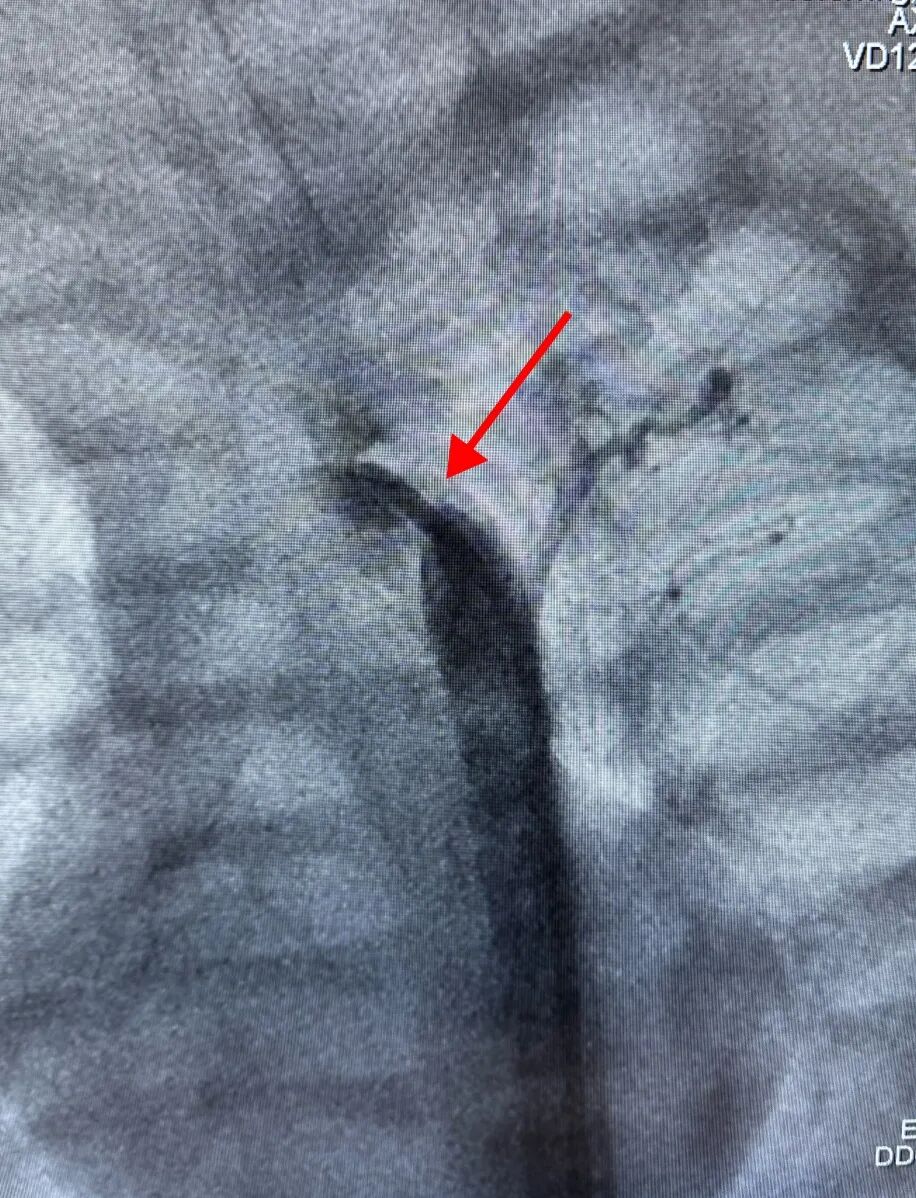

心导管室内,介入团队全神贯注,屏息操作,精准地将球囊送至预定位置。

每一个步骤都如履薄冰,每一个决策都关乎存亡,整场手术仿佛一场在方寸之间的精细雕琢。

扩张、观察、再评估......

“成了!”导管室外,团队成员看着影像说道。

主动脉最狭窄处由1mm扩张到近6mm,压差几乎为零,血流恢复了畅通,那条被堵塞的“生命主干道”终于被成功打通。手术成功!